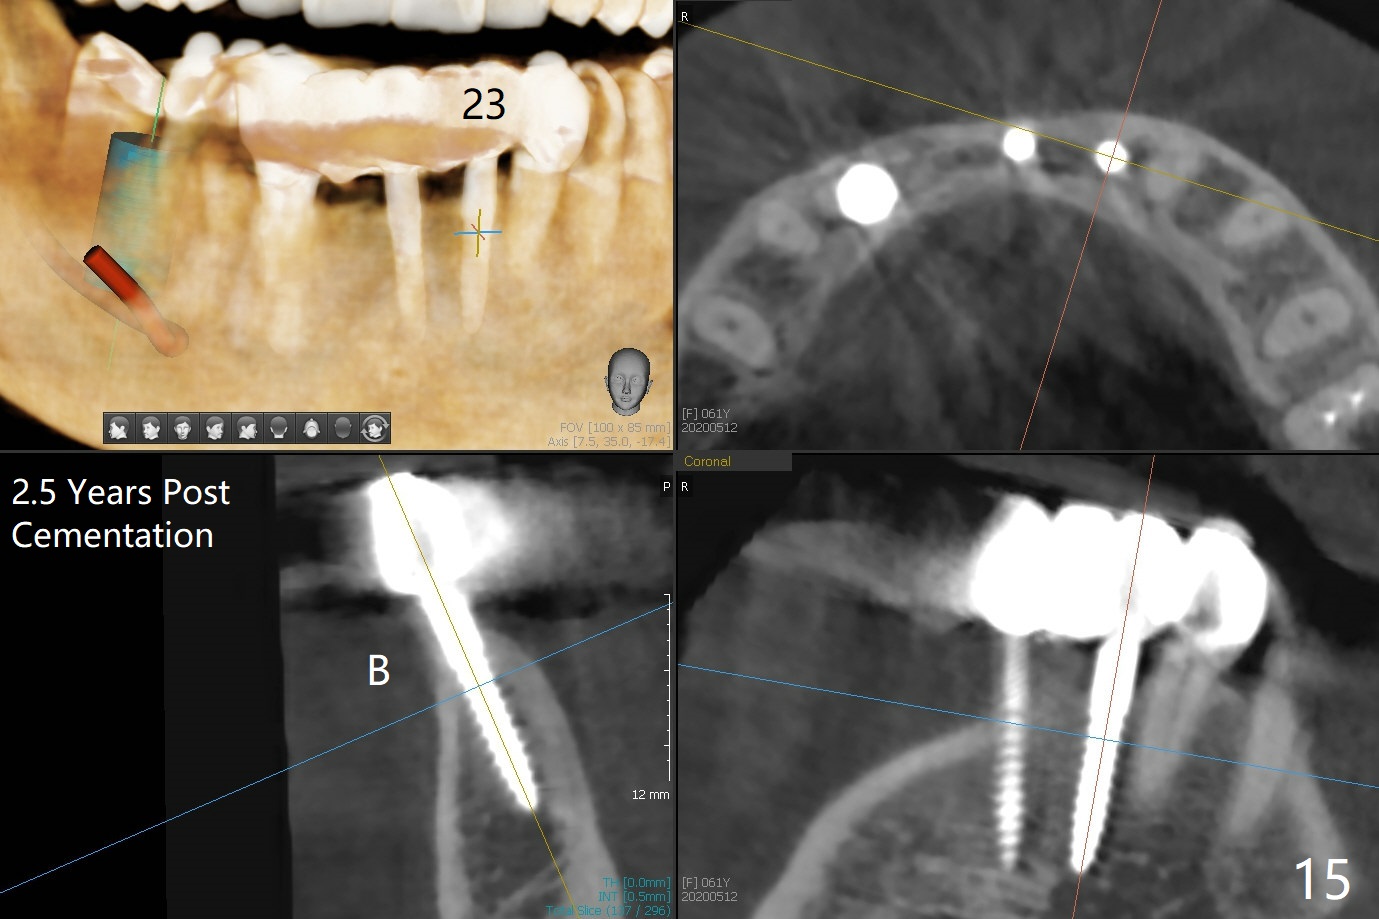

The mesial defect at #27 appears to have been repaired 8 months postop (Fig.8,9 *); there is no bone loss at 1-piece implant sites. The gingival recession seems to remain the same before and after removal of the provisional FPD (Fig.10,11). The bulging abutment at the cervix is less prominent when a straight abutment is used and prepared (Fig.12, 4.5x5.5(5) mm). There is no bone loss at #23, 25 and 27 sites 2.5 years post cementation (Fig.12-15), although the trajectory of the implants could be improved by using surgical guide (Fig.16-18).